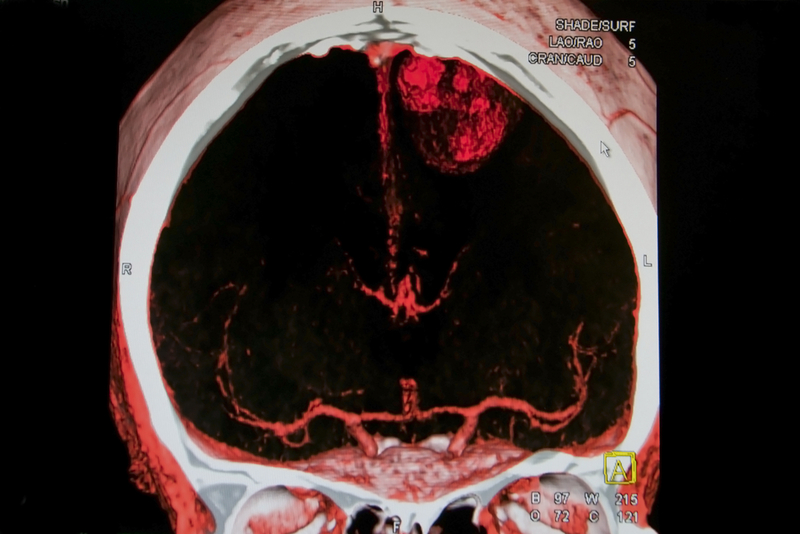

The search for treatments for spontaneous intracerebral hemorrhage, the most devastating type of stroke, which carries a 40% mortality rate, has been rife with disappointments. But a new study suggests that intensive blood pressure lowering may reduce the amount of bleeding in deep areas of the brain in patients with the condition, a team of Yale researchers report May 13 in the journal JAMA Neurology.

Although blood pressure reduction was associated with less ongoing bleeding, the analysis did not find an improvement in clinical outcomes. “This analysis demonstrates biological proof-of-concept of intensive blood pressure reduction as a therapy for intracerebral hemorrhage,” said Audrey Leasure, a second-year medical student at the Yale School of Medicine and lead author of the study. She said that larger studies of the subset of patients with damage to those areas of the brain may show improved therapeutic outcomes from intensive blood pressure reduction and that the specific location of brain injury should be incorporated into the design of future trials of brain hemorrhage.